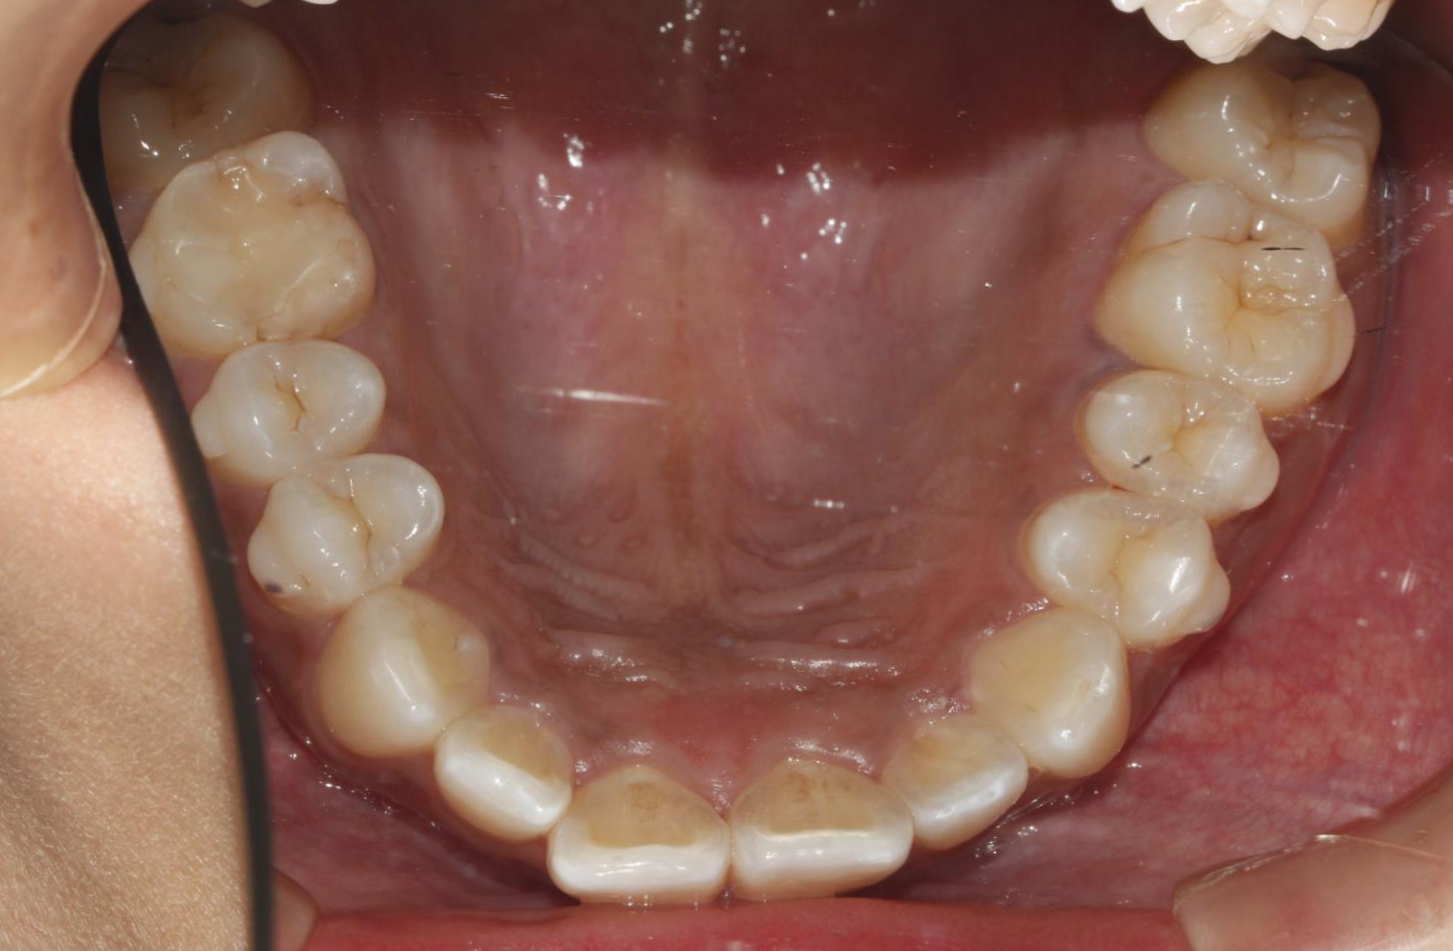

디테일한 치아 조절이 어렵다보니, 치아가 가지런하게 배열은 되지만, 가까이 들여다보면 치아배열이 조금 비뚤 수 있다.

한 가지 아이러니한 상황이 생기는데, 투명교정은 부정교합이 심하지 않은 부분교정 환자에서 많이 사용하는데,

마지막에 이런 미세한 부분은 고치지 못하게 되니 불만족스러워하는 환자들이 꽤 발생한다.